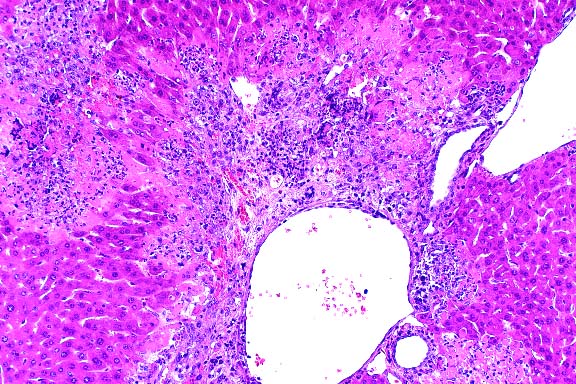

- Contributor's Diagnosis and Comments: Carcinoma, scirrhous,

seminal vesicle.

10x

obj

- Case 15-2. Seminal vesicle. The submucosa is heavily

infiltrated by pleomorphic epithelial cells. Both mucosal papillary

fronds and submucosa have an abundant inflammatory (neutrophilic)

infiltrate.

40x

- Case 15-2. Seminal vesicle. Pleomorphic tumor cells,

which are admixed with neutrophils in the submucosa may contain

multiple nuclei or variably sized vacuoles which displace the

nucleus peripherally (signet ring cells).

- Conference Note: Replacing most of the normal glandular

parenchyma and compressing the adjacent coagulating gland is

an unencapsulated, densely cellular, expansile, lobular neoplasm

composed of polygonal cells arranged in nests, cords, papillary

fronds, and glandular structures, separated and supported by

a moderate to coarse fibrovascular stroma. Frequently, the nests

and fronds of neoplastic cells are surrounded by abundant, immature,

fibrous connective tissue (desmoplasia). The glandular ducts

sometimes contain small amounts of amorphous, brightly eosinophilic

secretory material and/or degenerate neutrophils. Neoplastic

cells have variably distinct cell borders with small to moderate

amounts of basophilic to amphophilic cytoplasm, and irregularly

round to oval nuclei that are vesicular or have stippled chromatin,

and one to three magenta nucleoli. The mitotic rate is high,

and there are focally extensive areas of necrosis.